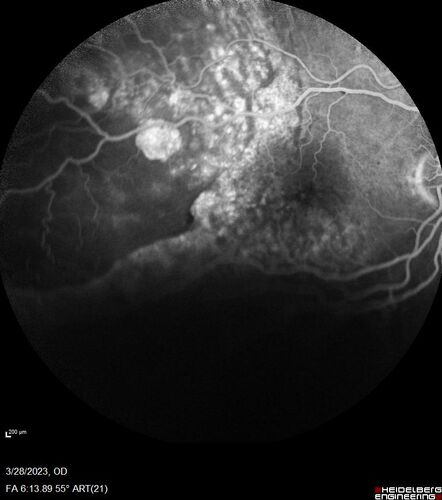

Choroidal Metastatic Breast Cancer with Exudative Detachment

58 year old female presented with 20/200 vision. Had 10 sessions of radiation and tumor shrank. The exudative detachment took almost a year to resolve. The vision improved to 20/40.